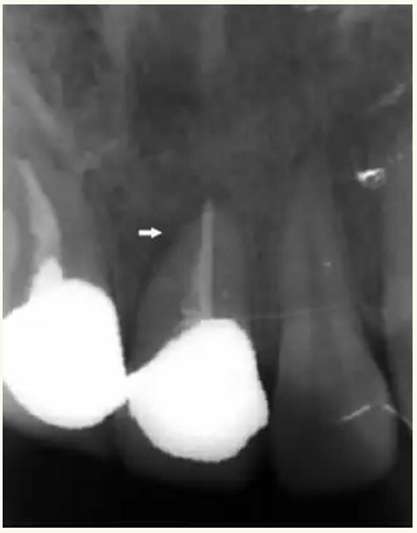

整個(gè)治療過程是在手術(shù)顯微鏡(Dental Operating Microscope)下完成,手術(shù)顯微鏡的應(yīng)用可增強(qiáng)根尖區(qū)視野,手術(shù)從骨切開、根尖搔刮、根尖切除、根尖洞形的制備至倒充填更加清晰,可減少組織的損傷和減輕患者術(shù)后疼痛和腫脹的發(fā)生率。手術(shù)顯微鏡具有良好的光源和放大作用,能準(zhǔn)確定位根尖部位,通過顯微口鏡的反射能夠清晰地觀察根尖切除的斷面,發(fā)現(xiàn)可能存在的根尖解剖變異,并能觀察根尖倒預(yù)備后的洞形,定點(diǎn)、定量輸送倒充填材料,以形成嚴(yán)密的封閉屏障,從而保證了整個(gè)手術(shù)順利完成?!?/span>

▲ 術(shù)前,21唇側(cè)牙齦距離齦緣2mm處及瘺管

▲牙膠尖示蹤顯示瘺管與此相通

▲21牙根近中側(cè)位于根尖1/3和根中1/3交界處有牙周膜間隙略增寬